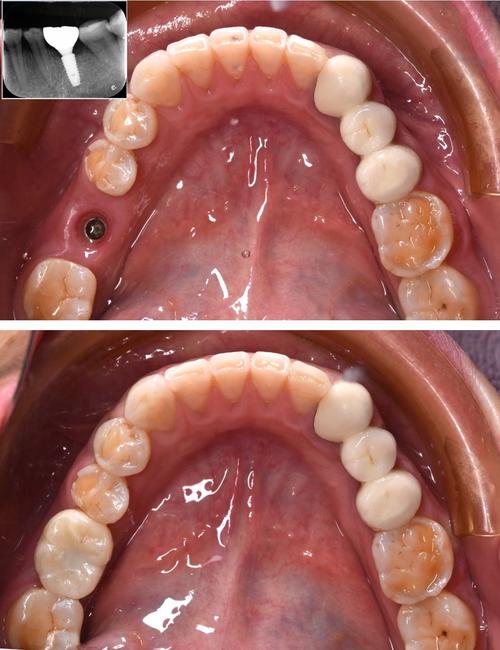

- 骨量评估: 这是最关键的一步,医生需要通过口腔锥形束CT(CBCT) 精确测量缺牙区的骨高度、宽度和密度,镶牙后缺牙时间越长,骨吸收通常越严重。

- 骨增量(植骨): 如果骨量不足,通常需要先进行植骨手术(如引导骨再生术GBR、骨劈开术、上颌窦提升术等),等待几个月让骨头长好(骨结合)后,再进行种植体植入,这大大延长了整个治疗周期(可能需要6个月到1年甚至更久)。